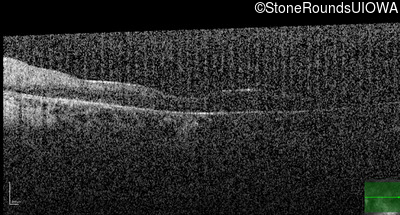

Optical Coherence Tomography - Right - 20/200 +2

Exemplar / OCT Stack